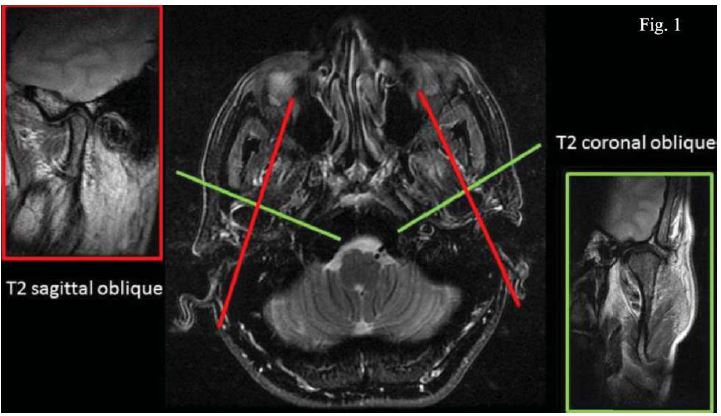

Todas las técnicas imagenológicas descritas previamente para la visualización y evaluación de tejidos blandos de la ATM no están exentas de dificultades. El desafío radica en la visualización correcta de las estructuras en esta área, ya que son pequeñas en relación al grosor de corte, además cualquier mínima variación en la alineación del plano pueden alterar la forma en que las imágenes se observan y por último, las estructuras de interés tanto en RNM como en TC normalmente no se ven en su totalidad, sino que para observarlas se deben ver cortes consecutivos23. Además la ATM se encuentra próxima a estructuras anatómicas como lo son las celdillas mastoideas, estructuras auditivas y al hueso temporal, pudiendo llevar a confusiones19. El protocolo sugerido incluye planos oblicuos sagitales, coronales perpendiculares y para- lelos al eje mayor de la cabeza condilar (figura 1), con un grosor de corte menor o igual a 3 mm y con una antena de superficie dual para poder captar la señal de ambas ATMs24-26. Se recomienda la aplicación de secuencias ponderadas T1, T2 con supresión grasa y densidad protónica tanto en boca abierta como cerrada26. La aplicación de un medio de contraste como el gadolinio se emplea para determinar la presencia de artropatías en ciertos pacientes27. Poco difundido es el estudio dinámico, el que se utiliza principalmente para la evaluación del disco articular y su relación con las estructuras óseas vecinas26.

Por último, debe considerarse lo descrito ya en el año 2012 por Shaefer et al.44 quiénes recalcaron la importancia del análisis de la RNM en cortes sagitales y coronales corregidos, métodos descritos anteriormente por Steenks et al.,45 y Chen et al.,46, ambos evidenciaron que la aplicación de parámetros funcionales podían mejorar la técnica para determinar el grado de desplazamiento discal. Esta modificación consiste en la observación del disco en cortes coronales paralelos a una línea perpendicular a la inclinación más posterior de la eminencia articular (figura 1).